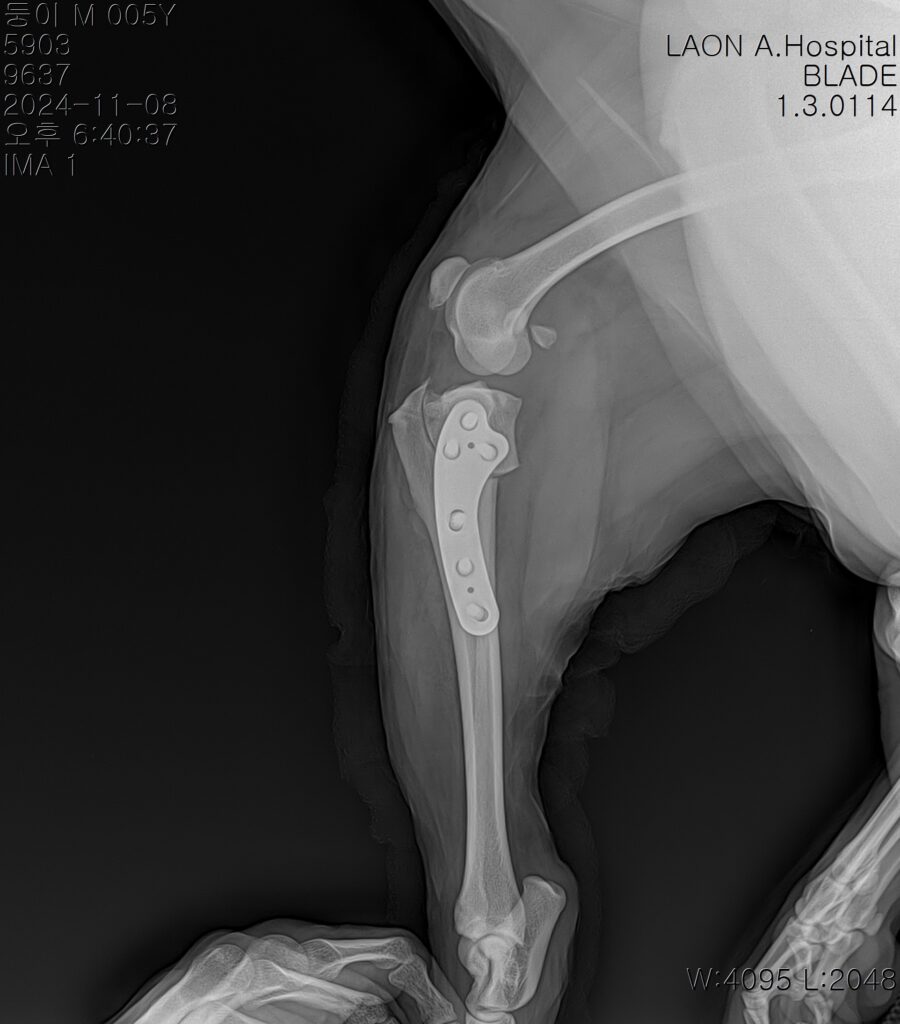

수술 후 방사선사진 / 출처: 라온동물메디컬센터

수술 후 약 1주간 입원 치료를 진행하며 초기 재활 프로그램도 함께 시작했습니다. 재활 초반에는 통증 조절과 부기 완화에 중점을 두고, 점차 체중 부하 훈련 및 관절 운동 범위 회복을 도왔습니다. 실밥 제거 이후 퇴원을 진행하였고, 퇴원 시 보호자님께는 재활 운동법과 생활환경 조절 방법에 대해 자세히 안내해드렸습니다.